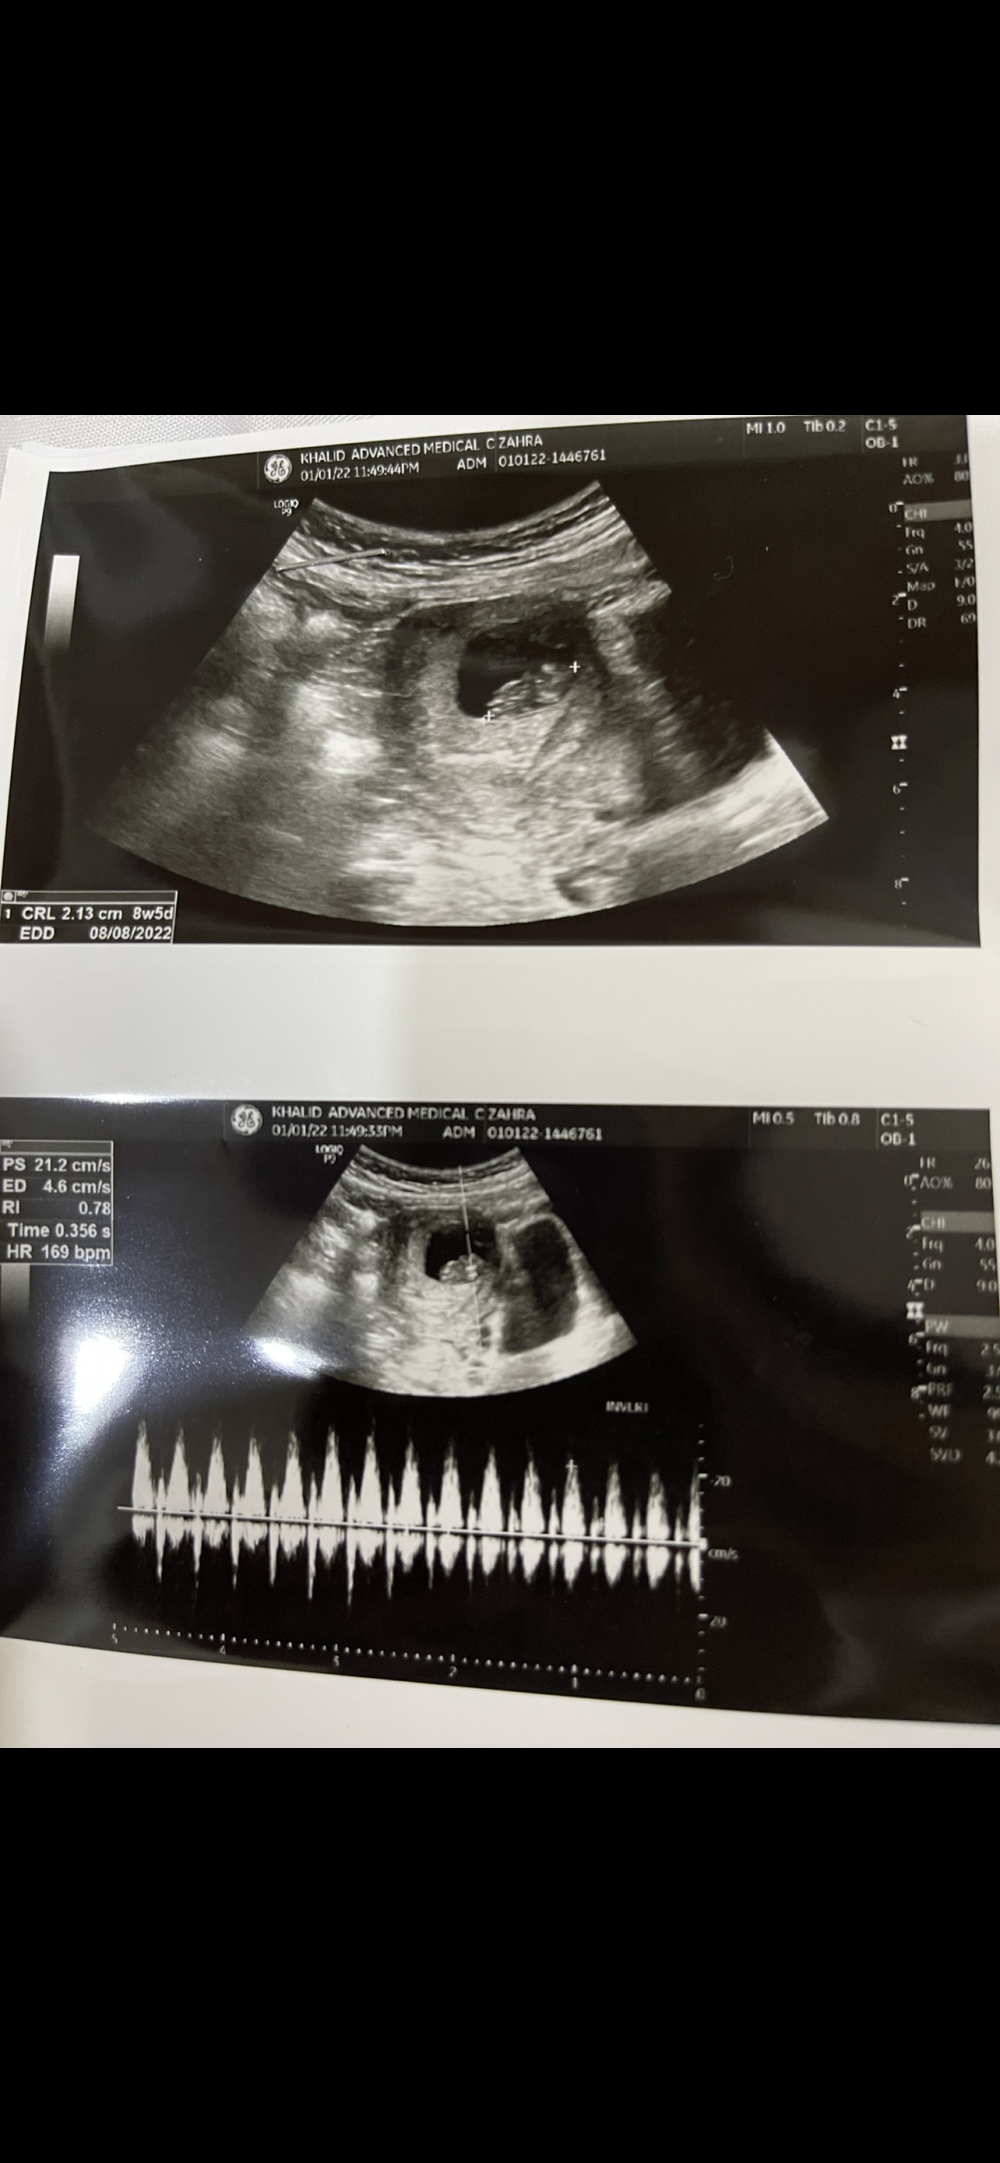

مساء الخير لي فترة ما دخلت التجمع مررت بظروف صعبة متنومة مع ولدي سوى عملية جدًا صعبة ربي يعديها على خير والى الان موجودين بالمستشفى لنا شهرين نفسيتي كانت تعبانة من التفكير والوحام وخنقة المستشفى حتى مراجعات عشان أطمئن على الجنين اخر مرة في الاسبوع التاسع ربي يحفظه قرأت بعض التجمعات اللي فاتتني ومبروك لكل من عرفت جنس الجنين و عقبال البقية ربي يتمم حملنا على خير يارب تواقه يا عمري ولادتي بتاريخ ٨/٨ وحبيت اسألك بما أنك من جدة فين سويتي السونار عند اي دكتورة و كمان بقية البنات اللي من جدة اذا تعرفوا دكتورة شاطرة أذكري اسمها وبأي مستشفى